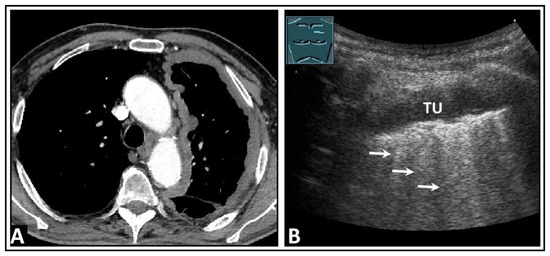

7. Other Pathologic Situations

8. Pleural Artifacts with Simultaneous Presence of Consolidation